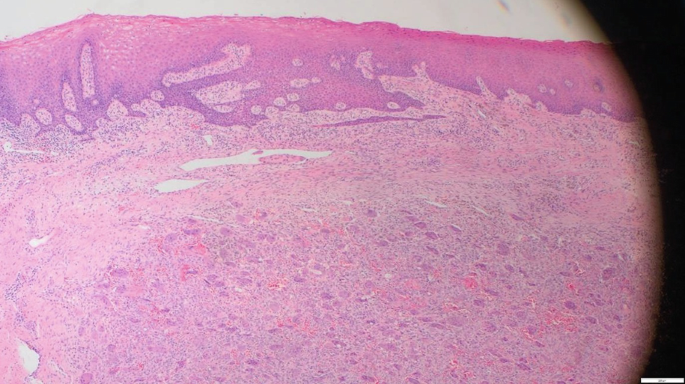

Peripheral Giant Cell Granuloma Histology

Histological appearance of peripheral giant cell granuloma ... Peripheral Giant Cell Granuloma : Giant Cell Epulis Pathology Outlines - Peripheral giant cell granuloma Rare Case of a Peripheral Giant Cell Granuloma of the Jaw as First ... Pathology Outlines - Peripheral giant cell granuloma Peripheral Giant Cell Granuloma Histology